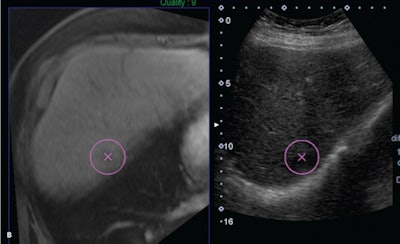

Software that fuses ultrasound images with MRI or CT studies can accurately guide liver biopsies for lesions that are hard to see on conventional ultrasound, yielding similar accuracy as CT-guided biopsy as well as some key benefits, according to an article in the June issue of the Journal of Ultrasound in Medicine.

In a retrospective study, a research team led by Dr. Yasmine Ahmed of University Hospitals Case Medical Center in Cleveland evaluated the performance of ultrasound fusion software, which enables interventional radiologists to view a patient's previously acquired CT or MR images side by side with the live ultrasound exam as they perform guided biopsies. Compared with CT-guided biopsy, ultrasound fusion-guided liver biopsy had a similar diagnostic yield, but it could be performed in about half the time and without exposing patients to additional radiation, according to Ahmed.

"When a limited screening evaluation of the liver using B-mode ultrasound showed lesions that were either invisible or hardly visible, a decision was made to switch to ultrasound fusion guidance instead," the authors wrote.